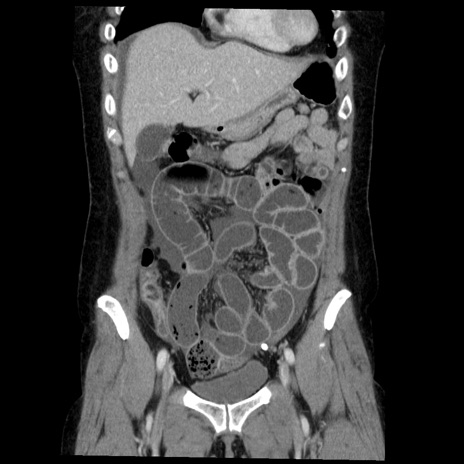

症例6(冠状断像)

【症例】50歳代女性

【主訴】下腹部痛

【現病歴】本日朝より下痢2回あり。 昼食を食べた後、嘔吐3回、下腹部痛認め、症状軽快せず、当院救急搬送。

最終食事:本日昼(生ものなし)。 昨日の夜、刺身を食ぺたとのこと。周囲に同様の症状の者なし。普段、排便は毎日あるとのこと。

【既往歴】卵巣癌術後(8年前に当院で卵巣摘出)

【身体所見】 意識清明、腹部:平坦、腸蠕動音→、やや硬、下腹部自発痛・圧痛あり、反跳痛あり、筋性防御なし。

【データ】WBC 16000、CRP 0.01